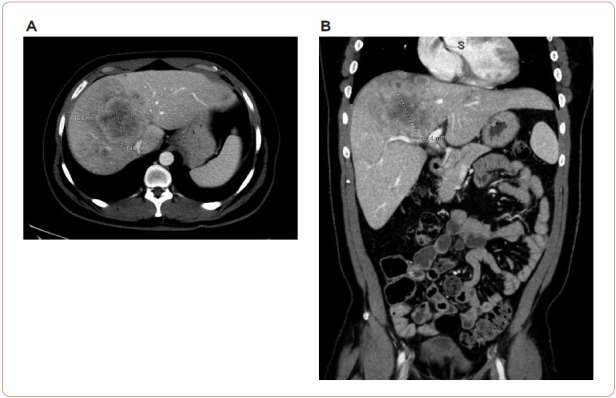

Aplastic anemia (AA) is a bone marrow failure disorder resulting in peripheral pancytopenia and marrow hypoplasia. An alternative diagnosis of hypoplastic myelodysplastic syndrome (MDS) can overlap this diagnosis but is differentiated by the presence of dysplastic progenitor cells. Since AA can be characterized as an autoimmune disease directed against hematopoietic stem cells, its presence can potentially increase susceptibility to alternate malignancies. Hypoplastic MDS, however, can present itself in an extramedullary fashion solely or as a relapse of acute myeloid leukemia resulting in symptoms similar to those described in this case study. Solid tumor malignancies may also result in abnormal blood counts, creating a wide differential diagnosis. This manuscript presents a case of untreated AA in a patient presenting later with severe abdominal bloating.